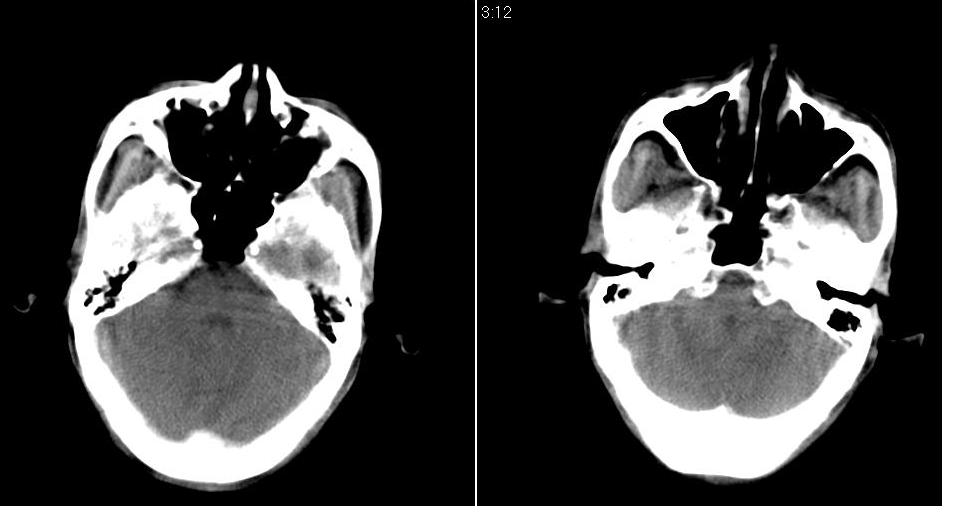

男 70岁,右侧颈部包块八个月余,下午及夜间疼痛加剧,包块质硬。化验穿刺镜下可见大量成堆裸核上皮细胞,可符合结核性淋巴结炎。

右侧颈部不规则软组织密度肿块影,密度均,边缘不清,颈筋膜间隙闭塞,向内致口喉咽受压变形,外达胸锁乳突肌深部,与之分界不清,周围骨质未见异常。